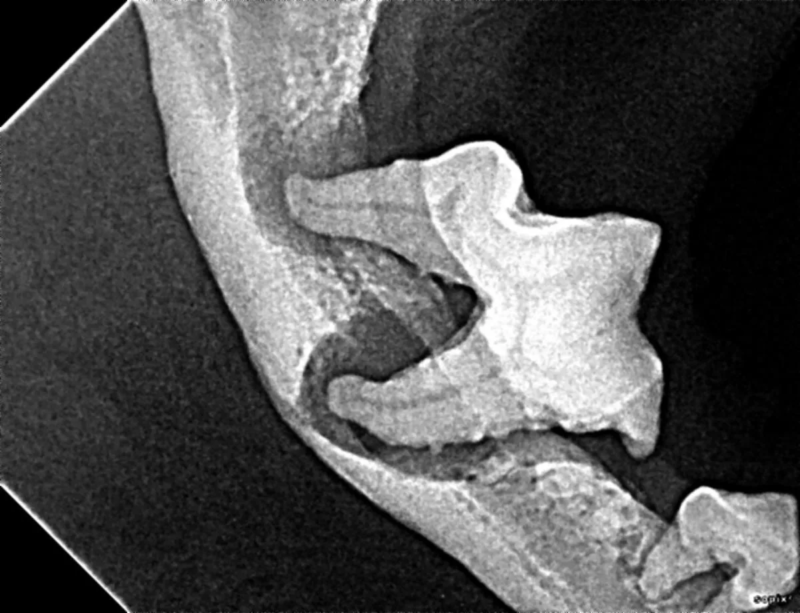

The Center now provides advanced imaging via cone beam CT. Cone beam CT is excellent for visualization of bony structures of the skull, nasal cavity, teeth, and ears. Cone beam CT is especially helpful for diagnosing dental disease and evaluation of jaw fractures. It can also be useful for evaluating the sinuses and tympanic bulla. Cone beam CT can be used in conjunction with nasal biopsy and culture to evaluate nasal discharge whether chronic or acute.

Tooth resorption is a disease process where the body begins to break down the adult tooth. It is widely known to occur in cats but can also occur in dogs. In cats these lesions are thought to be inflammatory, while in dogs they can be more of a replacement resorption process. These lesions can be very painful and should be treated, generally with extraction depending on the type of resorption that is occurring. The disease can be progressive and affect many teeth over several years. It is important to have regular checkups and yearly dental cleanings to monitor for these lesions.

Pets can be involved in trauma that can cause fractures to their head, teeth, and jaw bones. Correctly repairing these fractures is extremely important for your pet to have normal function of their mouth. If a jaw fracture is allowed to heal in an abnormal position, your pet may have great difficulty chewing and can be in significant pain. Many fractures can be successfully treated with minimally invasive oral procedures, but more complicated cases may require bone plating techniques. The Center offers cone beam CT imaging which provides extremely detailed images of the bones of the head and skull. Advanced imaging with CBCT facilitates selection of the best surgical technique to get your pet back to eating and comfort as soon as possible.